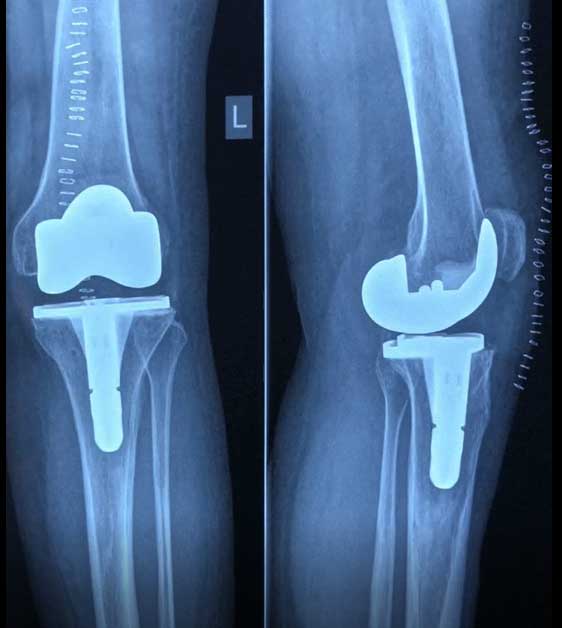

Total Knee Replacement